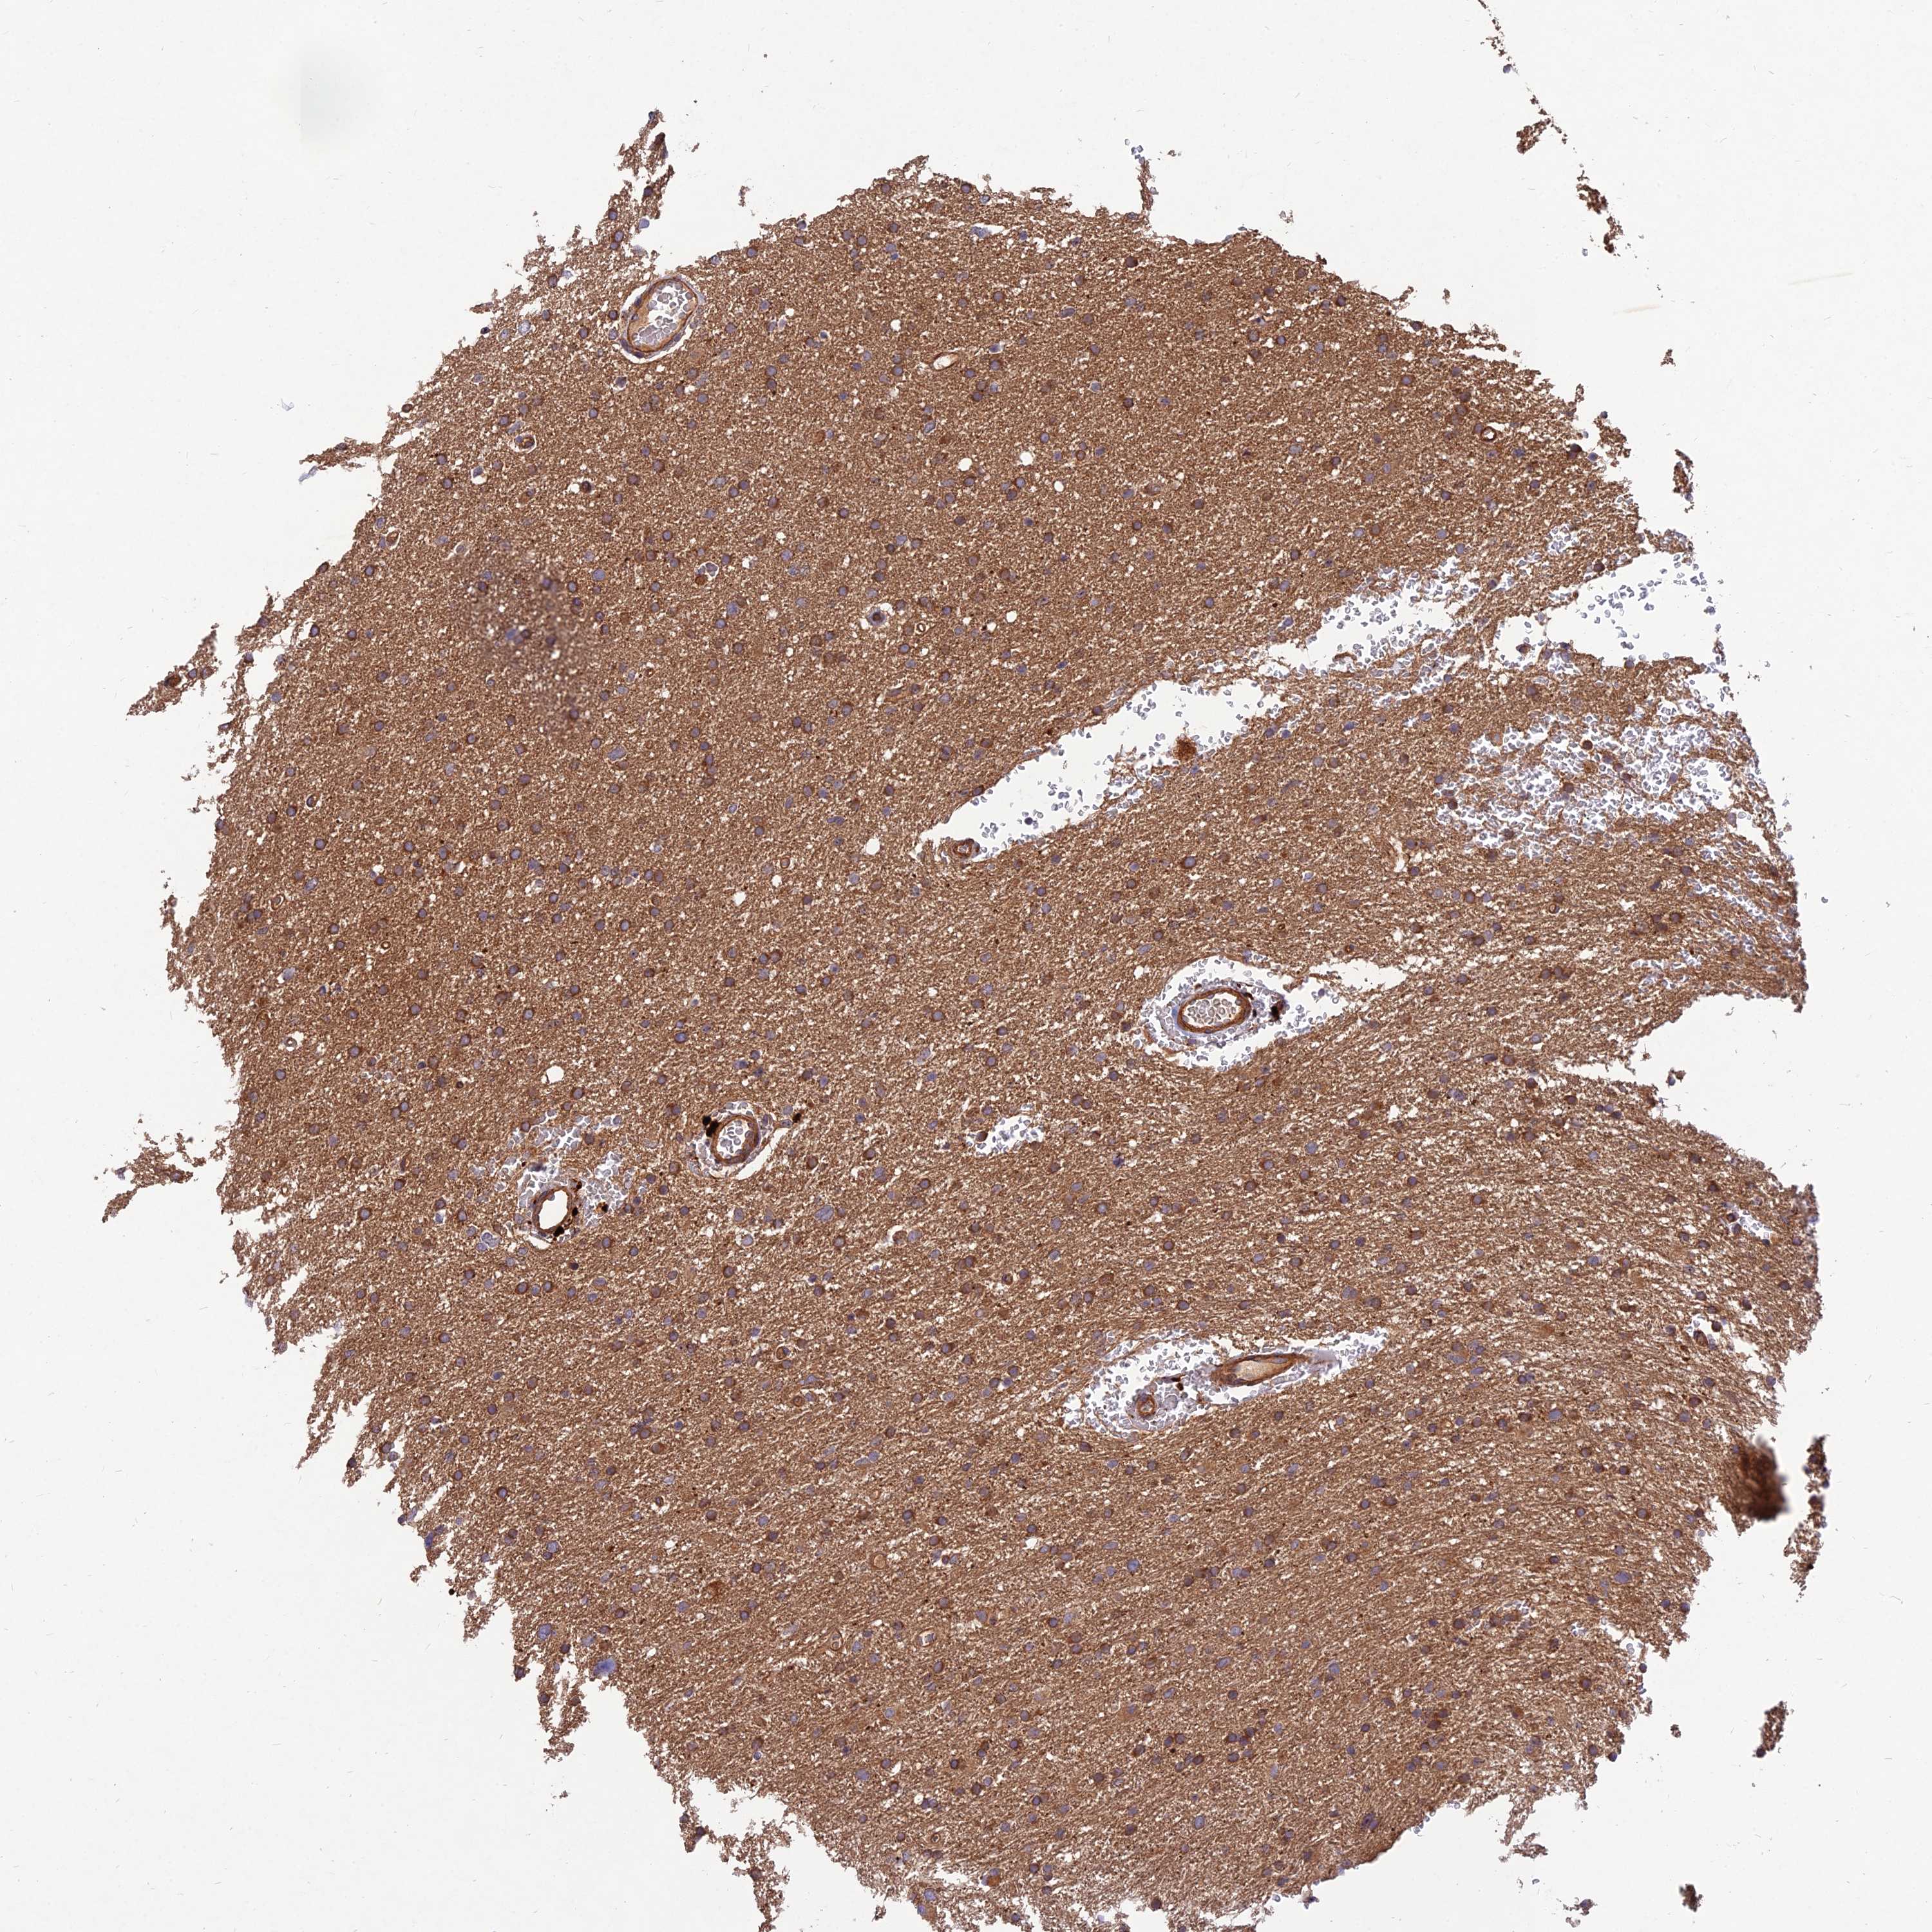

GLIOMA - Protein expressioni

A mouse-over function shows sample information and annotation data. Click on an image to view it in a full screen mode. Samples can be filtered based on level of antibody staining by selecting one or several of the following categories: high, medium, low and not detected. The assay and annotation is described here.

Note that samples used for immunohistochemistry by the Human Protein Atlas do not correspond to samples in the TCGA dataset.

Antibody stainingi

Antibody staining in the annotated cell types in the current human tissue is reported as not detected, low, medium, or high, based on conventional immunohistochemistry profiling in selected tissues. This score is based on the combination of the staining intensity and fraction of stained cells.

Each image is clickable and will lead to virtual microscopy that enables deeper exploration of all samples and also displays staining intensity scores, fraction scores and subcellular localization as well as patient and tissue information for each sample.

Antibody HPA039708

Antibody HPA040038

Staining

High

Medium

Low

Not detected

Intensity

Strong

Moderate

Weak

Negative

Quantity

>75%

75%-25%

<25%

None

Location

Nuclear

Cytoplasmic/membranous

Cytoplasmic/membranous,nuclear

Glioma, malignant, High grade

Glioma, malignant, Low grade